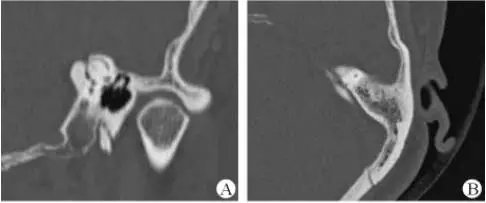

醫生若懷疑此病將會安排內耳CT掃描。在大多數案例中,一旦此病被耳鼻喉科醫生或其它聽力健康專家確診,則可實行手術治療。外科手術風險包含聽力損失以及神經損傷;重建及復原需內耳的治療以及大腦的重塑。

1、上半規管裂綜合征

內耳結構非常微妙。即使是內耳中大頭針樣的孔洞也能造成平衡失調。患者常常不敢進行如走路或轉頭的日常活動。此罕見疾病,醫學專家預估至少影響著人口的1%。可造成惡心,眩暈以及對噪聲極高的敏感性。病人還常常抱怨他們能聽到血管跳動的聲音。其中一位患者曾告訴耳科專家,他都能聽到自己轉動眼睛的聲音。